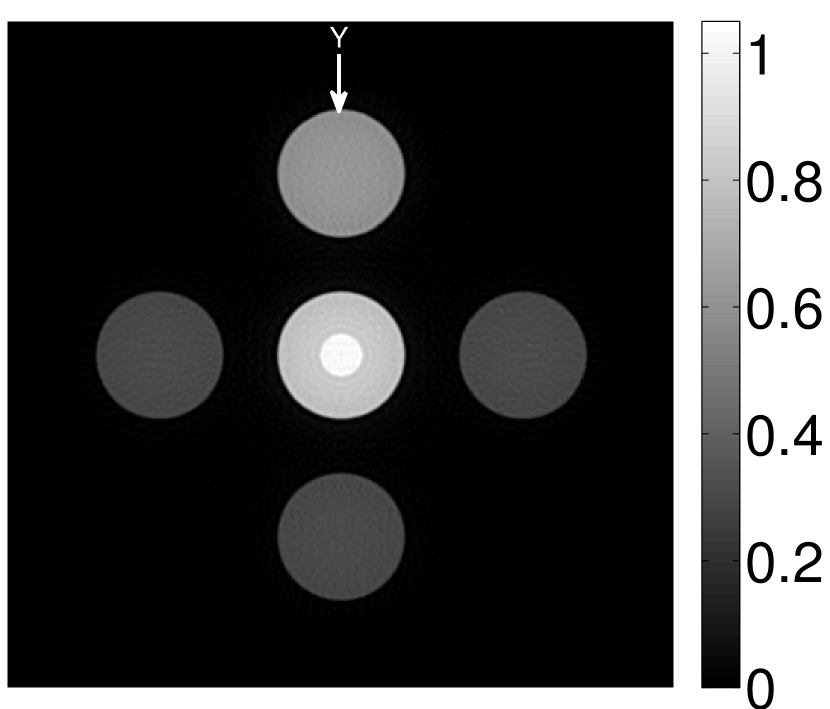

The numerical phantom shown in Figure 1(a) was employed. The phantom had a support area of mm2 and contained six uniform disks that were assigned different values of absorbed optical energy density.

A 2D circular measurement geometry was employed. transducers were evenly distributed on a ring of radius mm that enclosed the phantom. The SOS was assumed to be constant and set at mm/s. Since the simulated data were formed by use of the C-D imaging model in Eqn. (2), no inverse crime was committed. The components of this vector corresponded to equally spaced temporal samples over the interval s. Subsequently, the noiseless voltage vector was obtained by convolving the pressure data with EIR-1 in Figure 1(b).

The reconstruction region ( mm2) was represented by pixels with pixel size mm in each dimension. The initial guess of the EIR employed in the VP algorithm was different than the EIR that was assumed when generating the simulated data. This served to simulate a situation in which an experimentally measured EIR contained errors.

Each element in a real-world transducer array possesses its own EIR. In practice, the differences between the EIRs are sometimes neglected and an EIR corresponding to a single element may be used to represent all elements in the array. In some of the studies below, the EIR employed to initialize the VP algorithm (EIR-2 in Figure 1(b)) and the EIR employed to produce the simulated measurements (EIR-1 in Figure 1(b)) were experimentally measured from two different transducer elements in a circular transducer array (see Sec. VI-B). EIR-1 was measured by temporally integrating the PA signal produced by a point source positioned at the focus of the transducer. EIR-2 was measured by use of the method reported in [RNR2011]. In order to investigate the sensitivity of the VP algorithm to the initialization of the EIR, we employed different EIRs obtained by degrading EIR-1 as described later. When solving the sub-problem in Line-2 of Algorithm 1, was initialized as the zero vector. Algorithm 1 was terminated after 500 iterations, since it was observed that the changes in the reconstructed images with more iterations were negligible. When implemented by use of a single core of an Intel Xeon E5-2640 CPU, each iteration required approximately 7s to complete.

Figure 2(a) shows the image reconstructed by use of the conventional iterative method that utilized a system matrix based on EIR-2. Different values of the regularization parameter from the interval were considered. The reconstructed image with the value of that minimized the RMSE was chosen to represent the best performance of the conventional iterative method. Figure 2(a) and the profile in Figure 2(c) demonstrate that the use of an inaccurate EIR can result in strong artifacts and distortions in images reconstructed by use of the conventional methods.

When the VP algorithm was applied, different values of the regularization parameter from the interval and from the interval were considered. The image that minimized the RMSE was chosen and displayed in Figure 2(b). As revealed by this image and the profiles in 2(c), the VP algorithm yielded an image with fewer artifacts and distortions, and image fidelity was improved as reflected by the reduced RMSE.